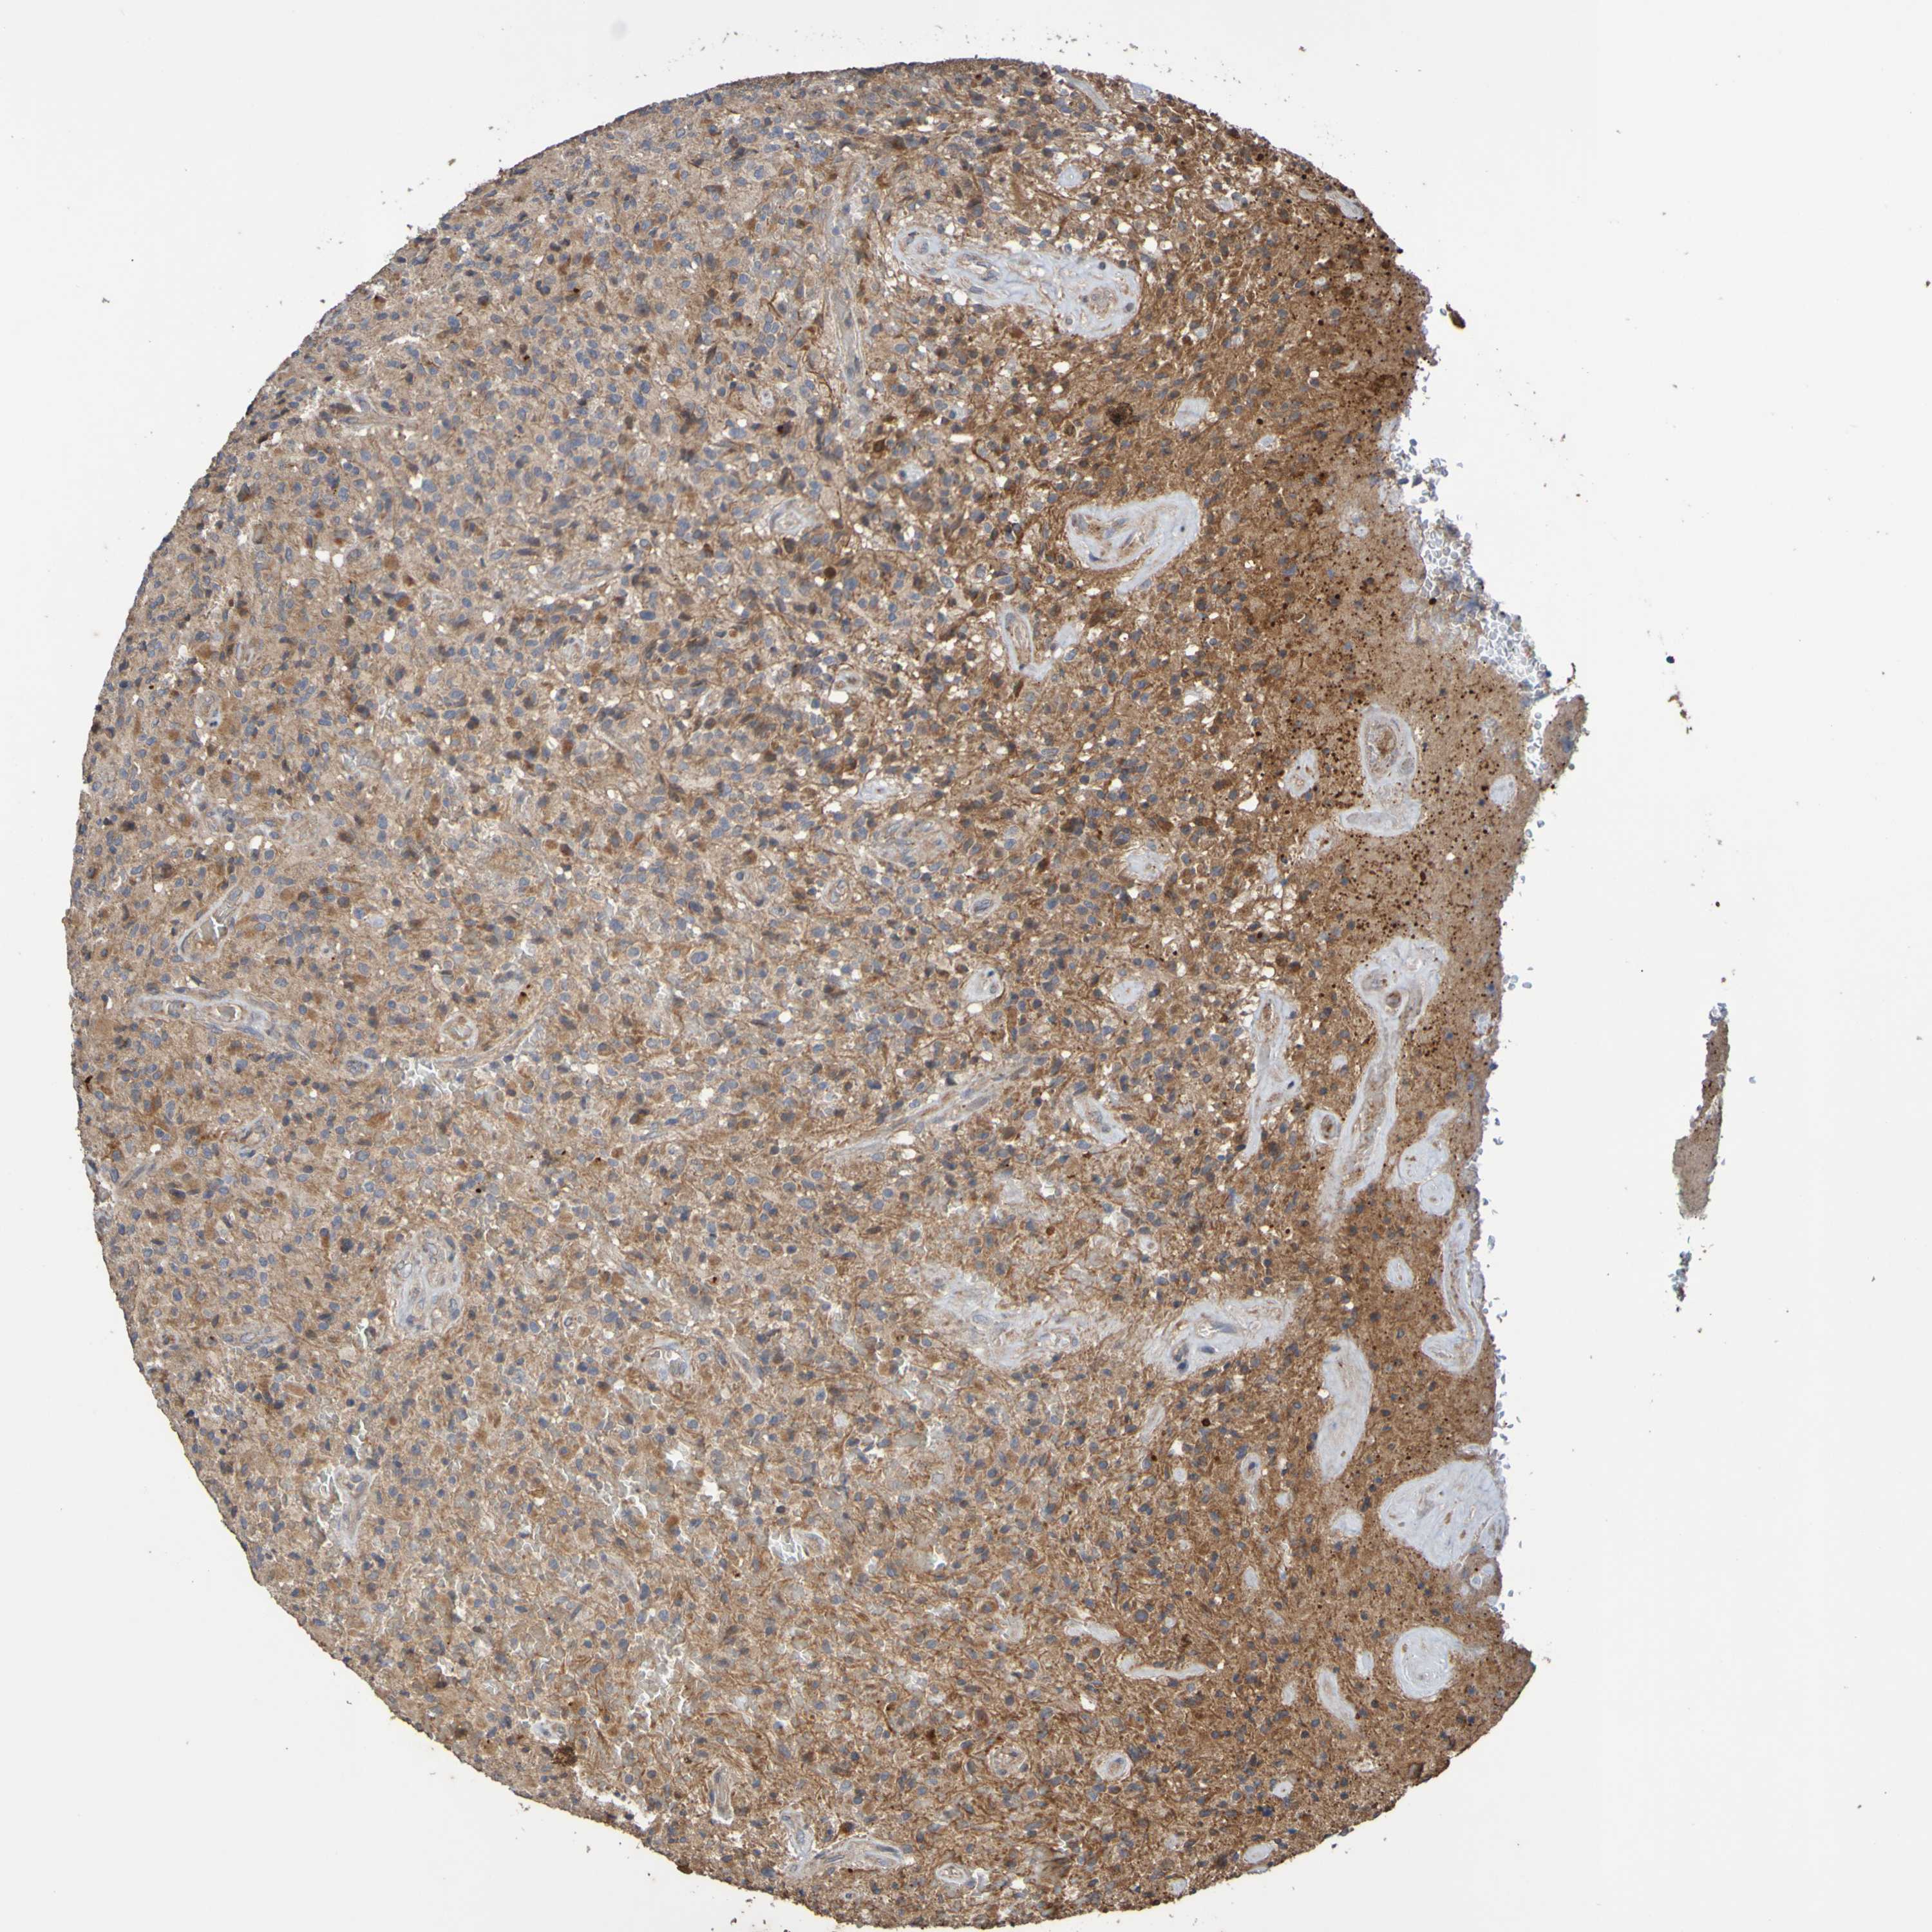

GLIOMA - Protein expressioni

A mouse-over function shows sample information and annotation data. Click on an image to view it in a full screen mode. Samples can be filtered based on level of antibody staining by selecting one or several of the following categories: high, medium, low and not detected. The assay and annotation is described here.

Note that samples used for immunohistochemistry by the Human Protein Atlas do not correspond to samples in the TCGA dataset.

Antibody stainingi

Antibody staining in the annotated cell types in the current human tissue is reported as not detected, low, medium, or high, based on conventional immunohistochemistry profiling in selected tissues. This score is based on the combination of the staining intensity and fraction of stained cells.

Each image is clickable and will lead to virtual microscopy that enables deeper exploration of all samples and also displays staining intensity scores, fraction scores and subcellular localization as well as patient and tissue information for each sample.

Antibody CAB010911

Staining

High

Medium

Low

Not detected

Intensity

Strong

Moderate

Weak

Negative

Quantity

>75%

75%-25%

<25%

None

Location

Nuclear

Cytoplasmic/membranous

Cytoplasmic/membranous,nuclear

Glioma, malignant, High grade

Glioma, malignant, Low grade